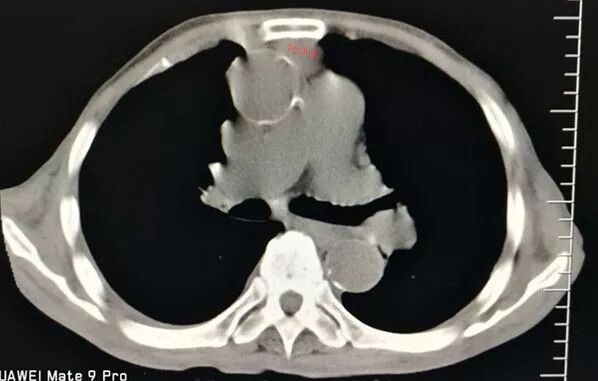

增強掃描顯示病灶與大血管關系密切!難度大、風險高!但沒有其它檢查手段或設備可替代穿刺活檢。

前有胸骨C,后有主肺動脈A、B,兩側有胸廓內動脈D、E遮擋,形成合圍之勢。